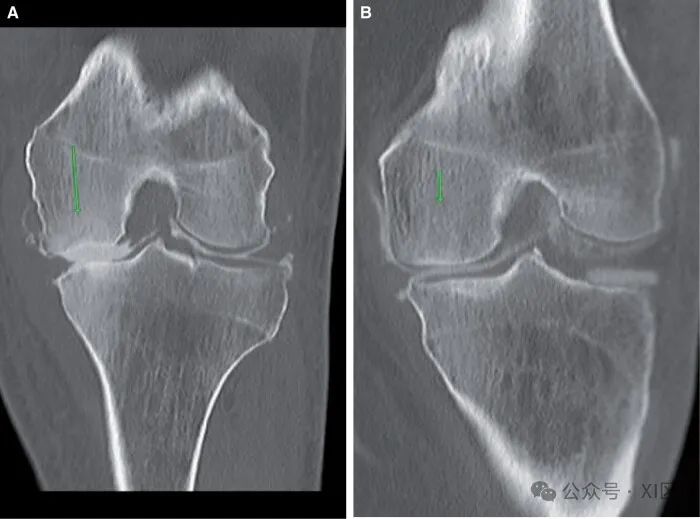

关节造影检查可发现偶然的骨肿瘤。在注射造影剂之前,应仔细筛查计划前图像中的任何骨骼病变。常见的成骨性良性肿瘤包括骨质外生瘤(图10A)、软骨瘤(图10B)、骨化性纤维瘤和纤维皮质缺损(图10C)。当对膝关节进行疼痛成像时,也可能偶然发现罕见的病理,如佩吉特病(图10D)。膝关节的自发性骨坏死表现为膝盖疼痛。预先计划的CT显示局灶性骨质增生,但无骨软骨缺损。对比后图像显示了骨软骨缺损的完整范围(图11A和B)。先前的关节造影(图11C)可用于显示骨软骨区域的急性变化。

图11 自发性骨坏死:(A)股骨内侧髁(箭头所示)的深部急性凹陷,伴有血性抽吸液。(B) 近一年前的关节造影图像,显示股骨内侧髁正常。滑膜肿瘤